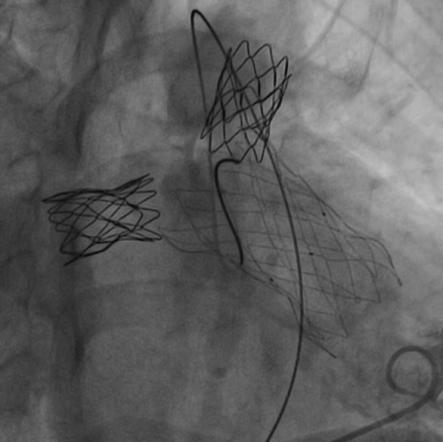

患者在全麻下,首先从左股静脉将造影导管分别送至右心室和肺动脉主干,行造影以明确右室流出道、肺动脉及肺动脉分支的基本情况。同时测量了右室流出道及肺动脉的尺寸。随后输送器通过右侧股静脉延加硬导丝将瓣膜输送到右室流出道,在X线的引导下,将瓣膜精确定位到植入部位并顺利进行瓣膜释放,无反流和瓣周漏,手术效果十分理想。

随着介入技术和介入材料的改进,通过经皮介入技术可以替代传统的外科手术。特别是肺动脉支架和肺动脉带瓣支架的应用,替代传统外科手术,可以起到非常好的效果。这2类支架,在同时出现狭窄和肺动脉严重反流时可以同时应用。一次性解决肺动脉分支狭窄和肺动脉反流问题。如果只有肺动脉分支狭窄,反流并不严重时,可以先处理肺动脉分支狭窄,也就是可以在狭窄部位植入Pul-Stent®肺动脉支架进行扩张。一旦解除了狭窄,也会延缓肺动脉反流的加剧。这样可以保护了右心功能,促使肺血管发育,而且会推迟肺动脉反流干预的时间。